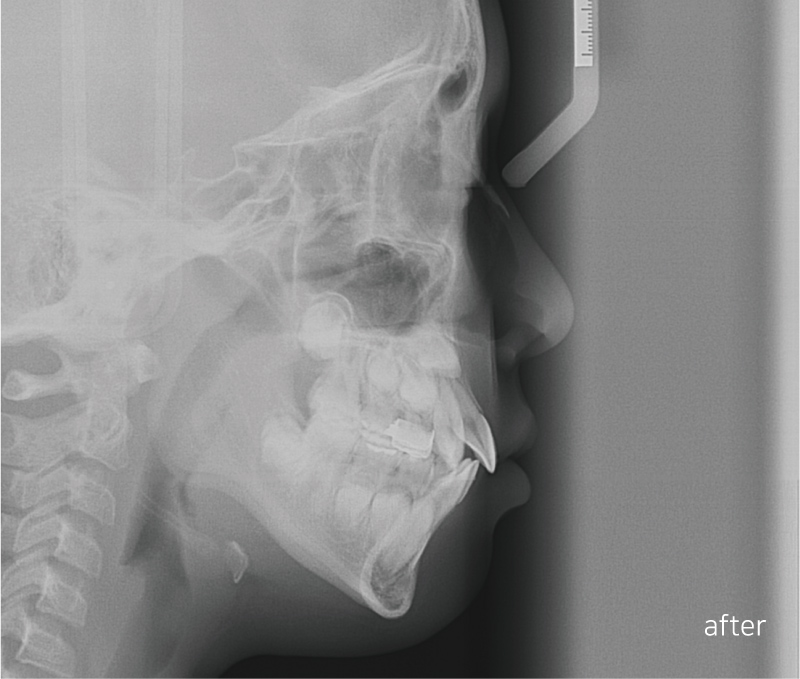

Before / after

상하악 Clippy-C (클리피씨) 전체 교정

안 모의 변화 모습이에요.

상/하악 전치 모두 상당량이 후방으로 이동이 되었기

때문에 훨씬 심미적으로 변화가 되었어요.

<24개월 교정 완료 모습>

전체적으로 치아가 크게 개선이 되었어요.